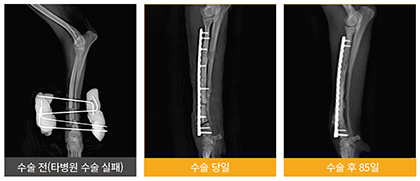

‘플레이트’와 ‘스크류’는 손상되거나 부러진 뼈를 빠른 속도로 회복시키는 데 뛰어난 효과를 보이는데, 골절이나 슬개골 탈구 등 시술 빈도가 높은 수의정형 분야의 새로운 획기적인 시술로 주목 받고 있다.

제일메디칼코퍼레이션의 ‘플레이트’와 ‘스크류’는 제품의 뛰어난 효과와 우수성은 물론 설계부터 세공, 특수세척 과정, 정밀 검사에 이르기까지 제조 과정부터 철저한 품질관리로 믿고 사용할 수 있는 안전한 제품으로 잘 알려져 있다.